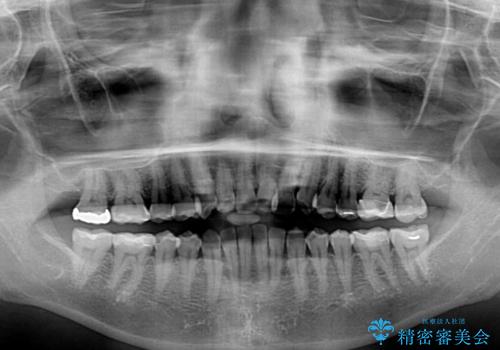

- 前歯のクロスバイトを気にして来院された患者様です。

上下ともに、前歯部を中心にやや叢生が認められる程度であったため、ワイヤーでもインビザラインでも、どちらでも対応可能な状態でした。

咬合力が非常に強く、治療が進むにつれて上下奥歯が離開してくることが予想されるため、治療途中から上下の顎間ゴムを使用することを理解いただき、インビザラインによる矯正治療を行うこととしました。